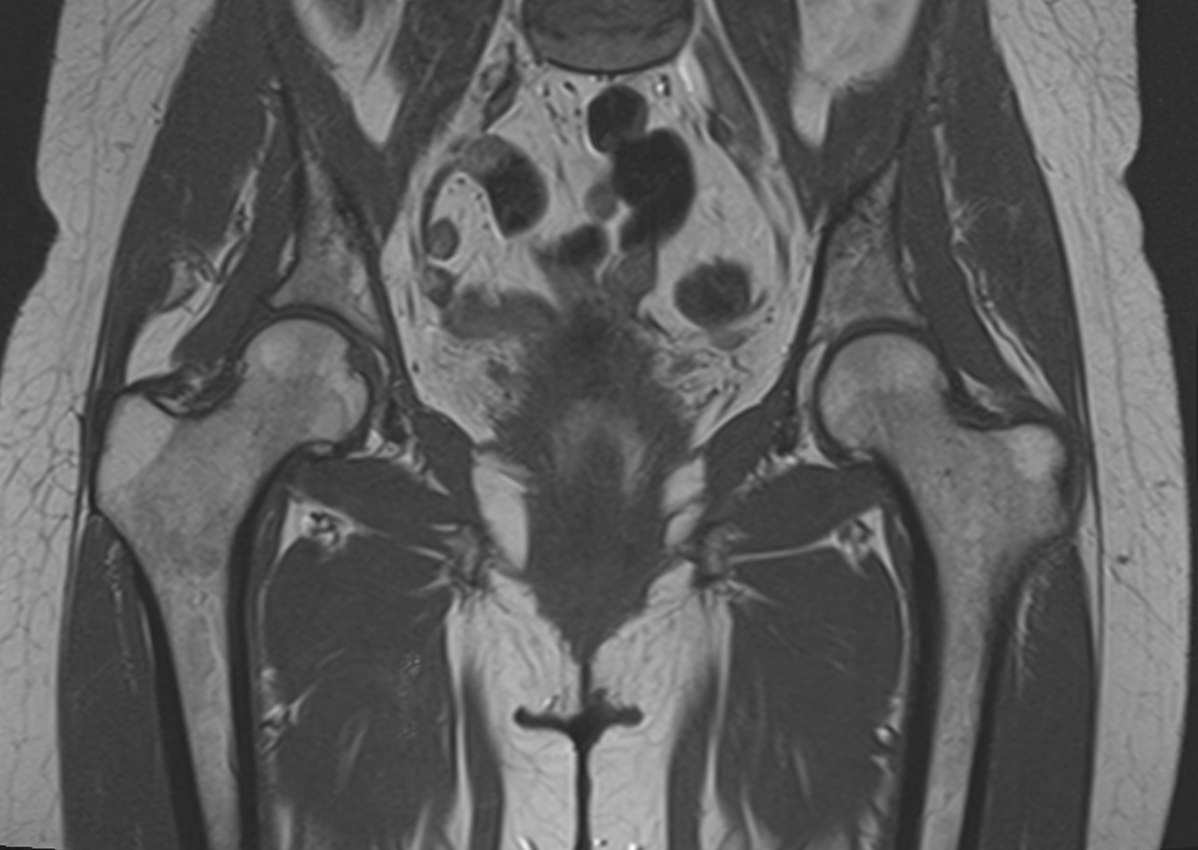

Максимально информативным способом диагностики заболеваний тазобедренных суставов является магнитно-резонансная томография. Кроме высокой информативности МРТ обладает такими преимуществами как достаточная быстрота, безболезненность, неинвазивность и безопасность. Метод основан на использовании действия на ткани внешнего магнитного поля, при этом не применяется вредное рентгеновское излучение. Поэтому МРТ можно проводить столько, сколько необходимо. Например, это бывает важно во время предоперационной подготовки и для динамического наблюдения в ходе лечения, в том числе, в послеоперационном периоде.

В клинике «Доступная медицина» МРТ тазобедренных суставов проводится на новейшем высокопольном томографе экспертного класса TOSHIBA VANTAGE TITAN 1,5 Тесла. Томограф производит сканирование зоны исследования, делая послойные срезы в разных плоскостях с шагом от 1 мм, затем с помощью цифровых приложений преобразует полученные данные в трехмерные изображения превосходного качества. МР томография дает детальную информацию о состоянии костных структур сустава, сухожилий, связочного аппарата, синовиальной оболочки, суставной полости, нервов, сосудов и прилегающих мягких тканей. Это позволяет поставить точный и достоверный диагноз и назначить вовремя лечение.